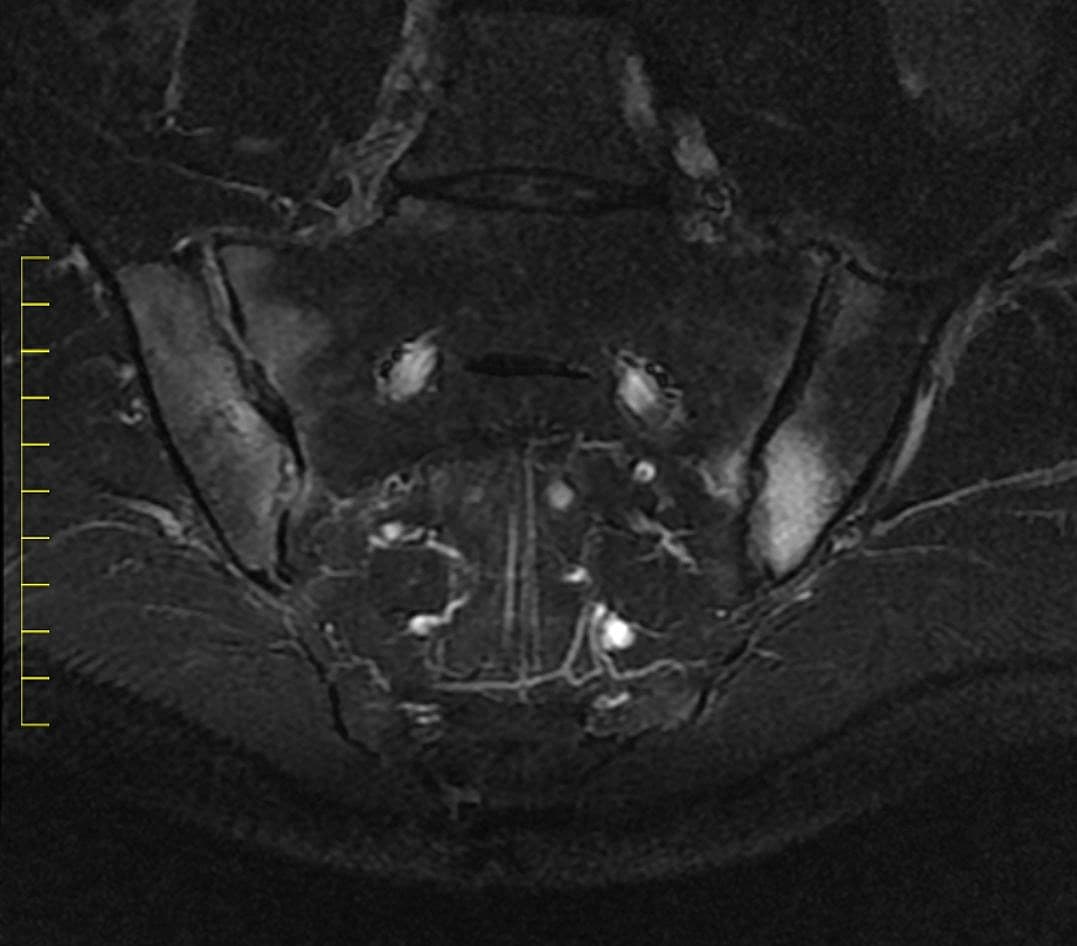

”MR- og ultralydsskanning har gjort en vældig forskel for behandlingen af især de inflammatoriske ledlidelser”, fortæller professor og overlæge i reumatologi ved Rigshospitalet Glostrup, Mikkel Østergaard:

”Især gælder det for leddegigt, psoriasisgigt og aksial spondylartrit – dvs. rygsøjlegigt, der i sin fremskredne form også er kendt som Morbus Bechterew”.

”Tidligere var man ikke i stand til at se forandringerne i ryg og bækken, fordi de ikke er synlige klinisk, og fordi de røntgenbilleder, som var den eneste tilgængelige billeddiagnostiske metode, kan først se forandringerne, når de har stået på så længe, at der er ødelagte knogler, led og ryg.”

”Med røntgenbilleder kan man ikke se den betændelsesproces, som man gerne skulle behandle. Men det er vildt afgørende, at man på et tidligt tidspunkt finder ud af, hvad der er galt og er i stand til at følge processen, hvis man skal gøre noget ved det”, siger Mikkel Østergaard.

”Før MR-skanningen – som er meget vigtig ved lidelser i ryg og bækkenled – gik der i gennemsnit 7-10 år, fra de første symptomer og til man kunne stille en diagnose. Det er altid godt at få en diagnose, så man ved, hvad man fejler. Men det er endnu bedre, hvis man kan gøre noget ved det”, siger Mikkel Østergaard.

”Da der i 2009 kom nye retningslinjer for at opdage rygsøjlegigt, fik MR-skanning en central rolle, og med den tidligere diagnose kunne man sætte behandlingen ind langt tidligere og dermed undgå en masse lidelser og funktionsnedsættelser”, siger han.

”Kombinationen af bedre diagnostik og bedre behandling var et gennembrud. I dag bruges MR-skanning rutinemæssigt til at afklare, om en patient har rygsøjlegigt, og der er ingen andre metoder, der gør det tilnærmelsesvist så godt”.

”Men en væsentlig ting var også, at MR- og UL-skanning langt mere følsomt end røntgendiagnostik og lægens hænder kunne konstatere, om der er betændelse i leddene, og om der er sket skade på knogler. Er der betændelse, kan man indlede behandlingen, og med den nye billeddiagnostik kan man tilpasse behandlingen undervejs”.